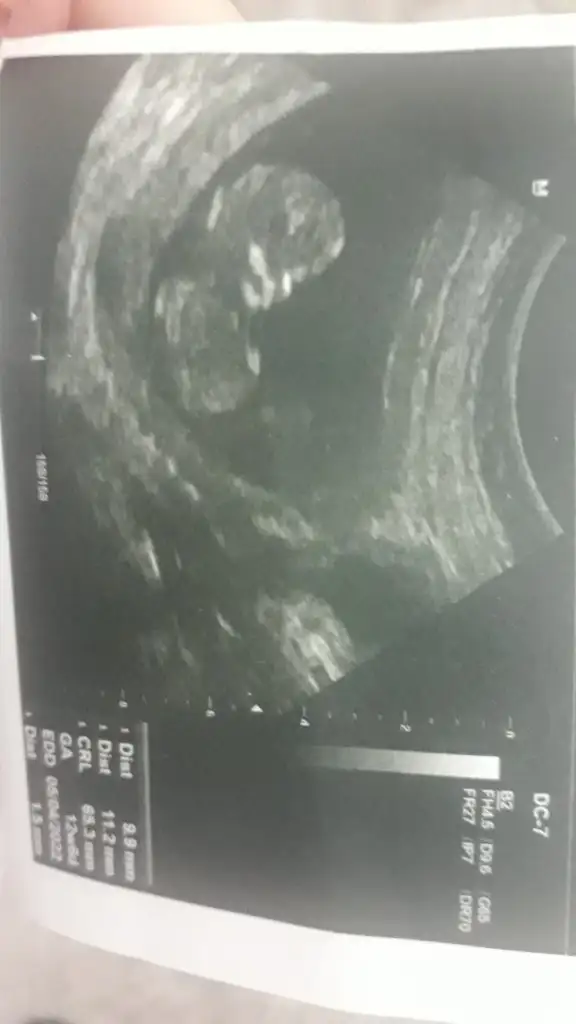

Banada tahmin yapabilir misiniz 12 haftalık

ttecrübeli bayanlar yorum yaparsaniz cok sevinirim...